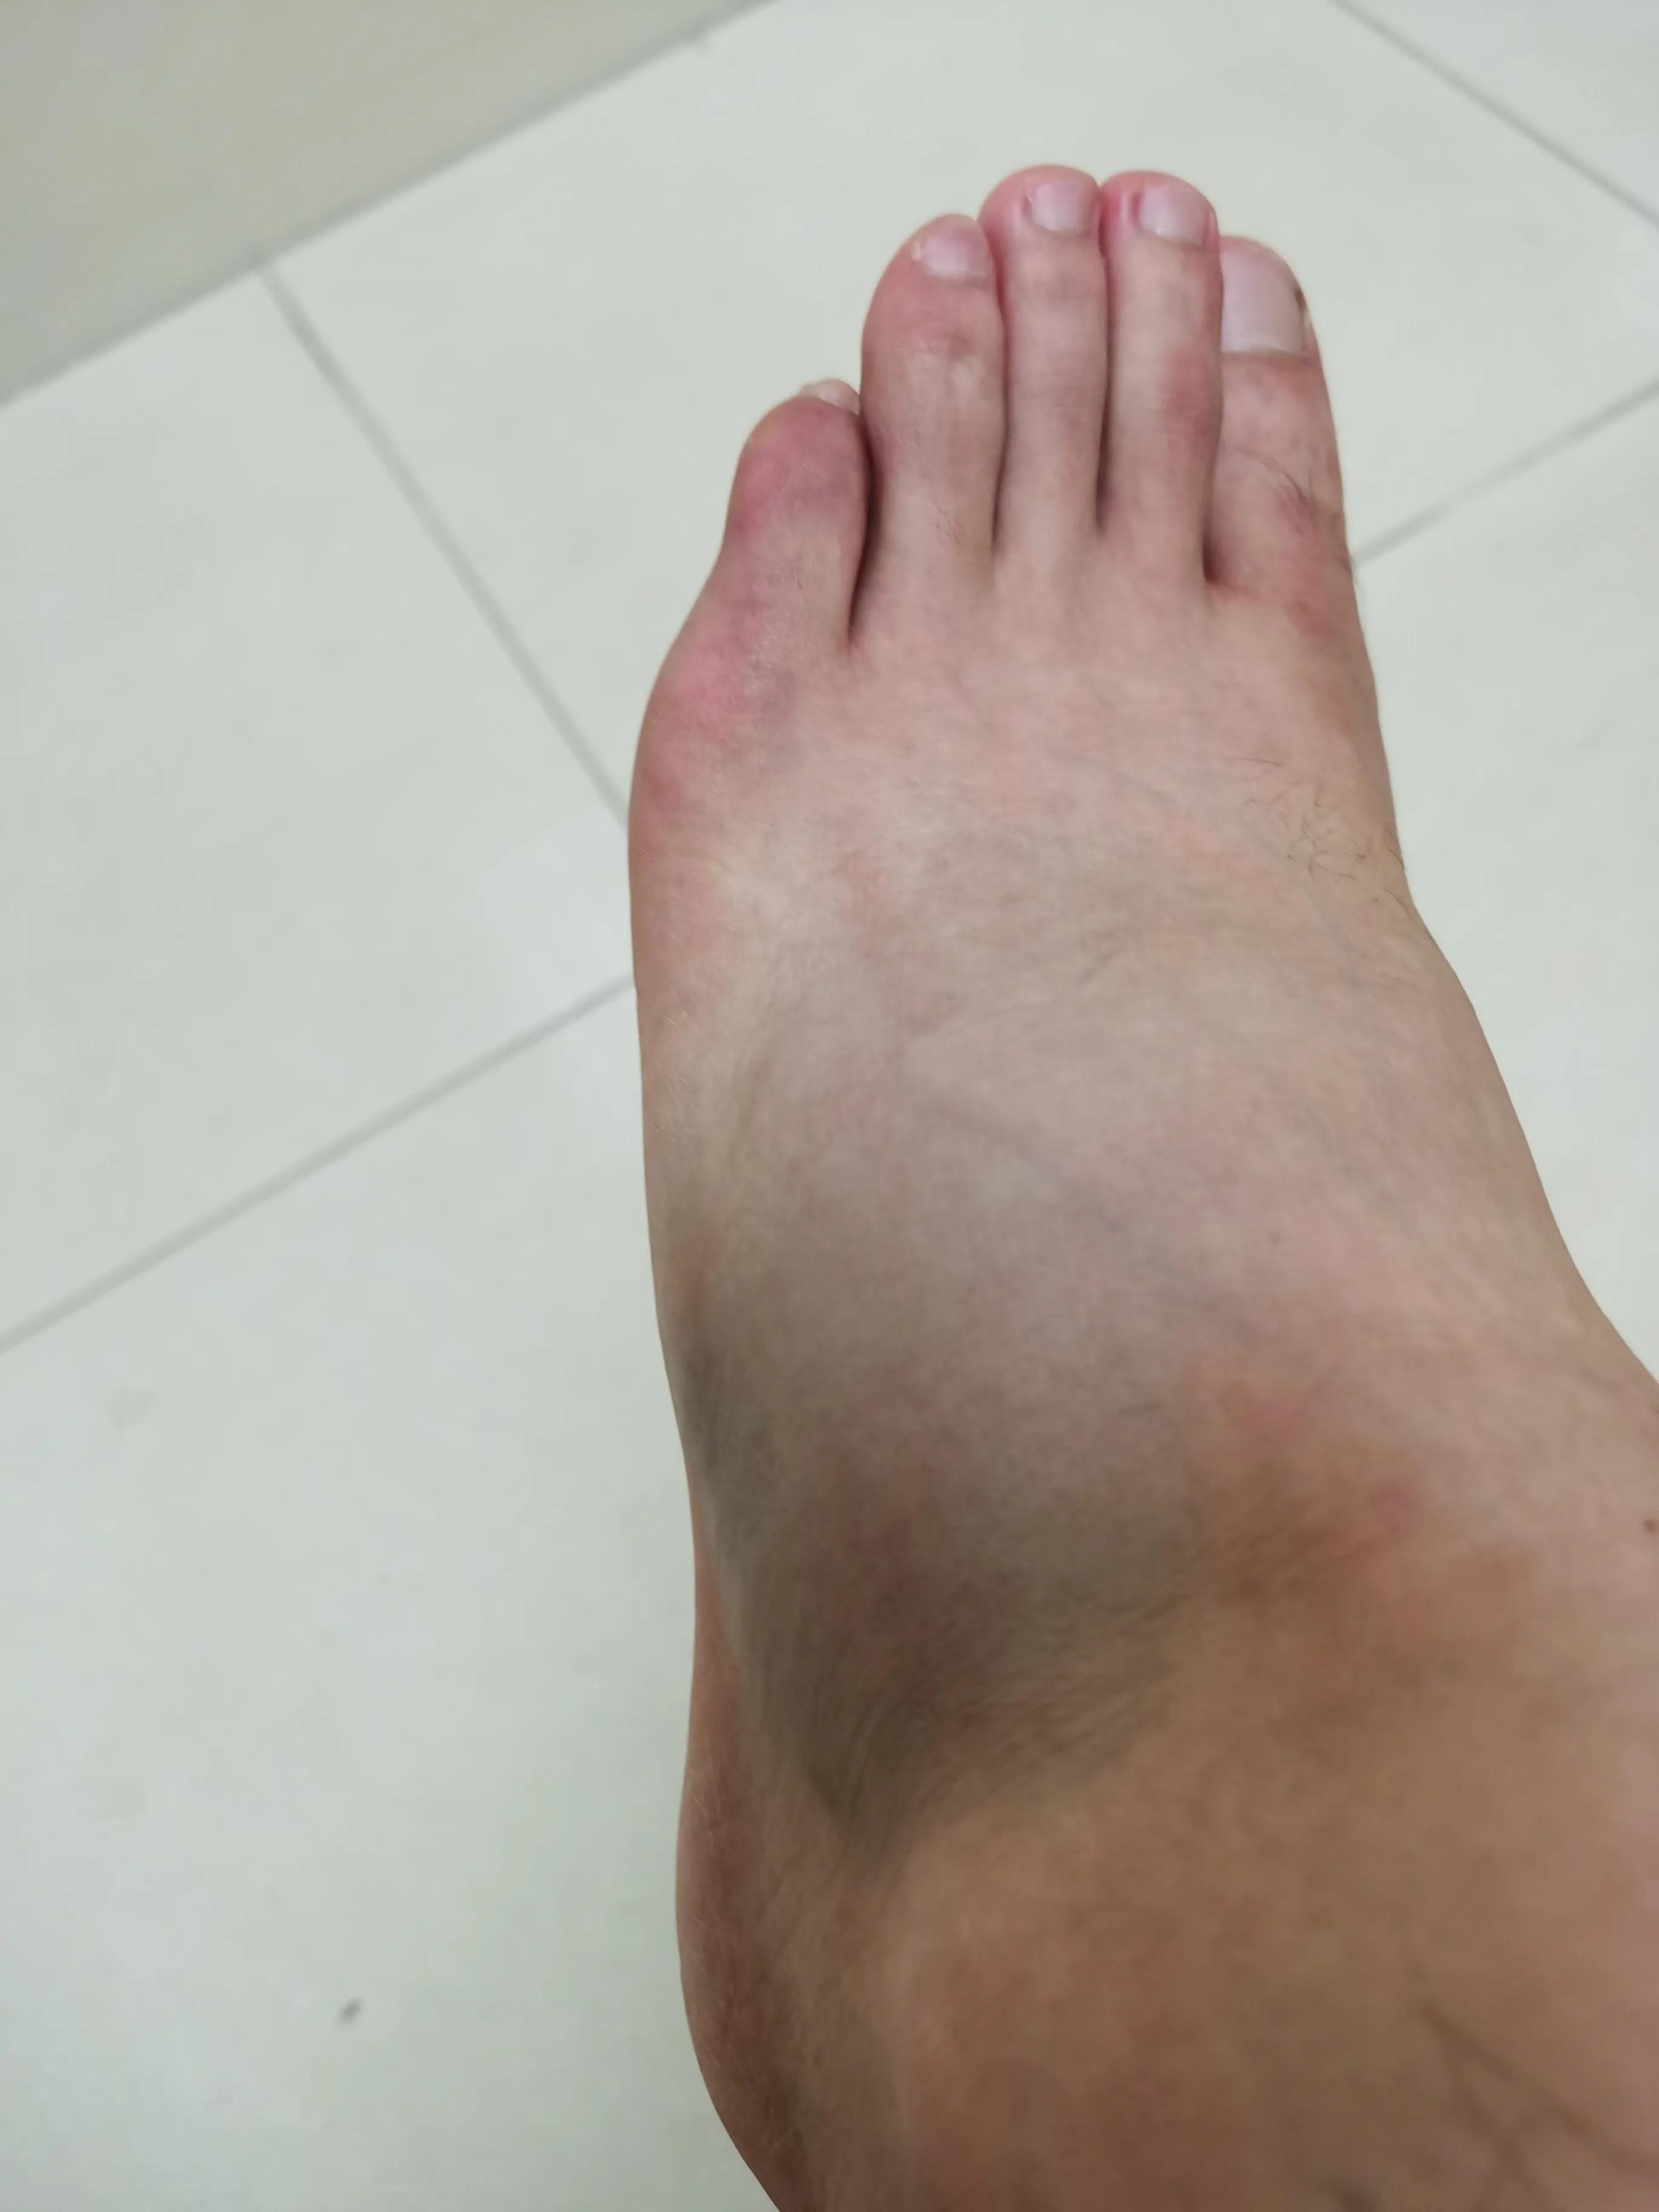

这是当晚九点多,距离骨折已经四个小时了,越肿越大

此时见面已经肿了很多,又重新抽血拍片检验,恰逢疫情各种不便

直到8月才基本散去,但是长时间放下脚还是会肿,躺床上的话,不垫高也还好,就是不能放下来,去医院路上肿的样子就不发出来了